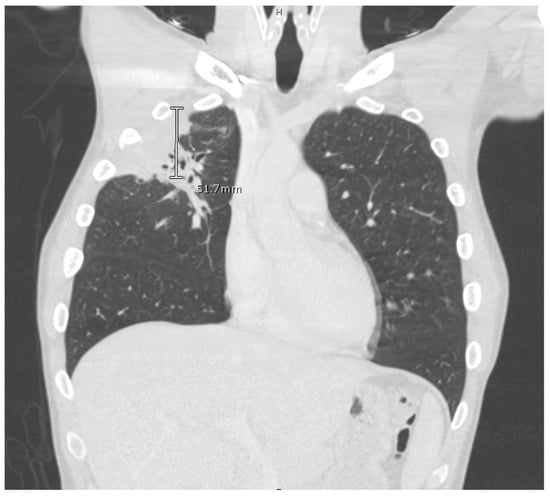

The computed tomography (CT) scan of his chest and abdomen revealed a right upper lobe cavitary lesion abutting the ribs (Figure 2) and a sinus tract from his left ischium to the skin over his left lower abdomen, respectively. Additionally, a CT scan of his head was also obtained, which demonstrated a mass extending from his right occipital skull with evidence of skull erosion as well (Figure 3).

Figure 2. CT scan of chest, right upper lobe pleural and subpleural consolidation with erosive changes at the 3rd and 4th ribs and involvement with the chest wall.